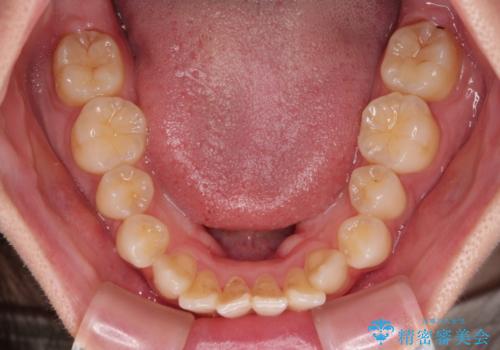

- 口元の突出感と口の閉じにくさを気にして来院された患者様です。

上下左右第一小臼歯4本を抜歯し、ワイヤー装置にて口元を引っ込めるよう矯正治療を行うこととしました。